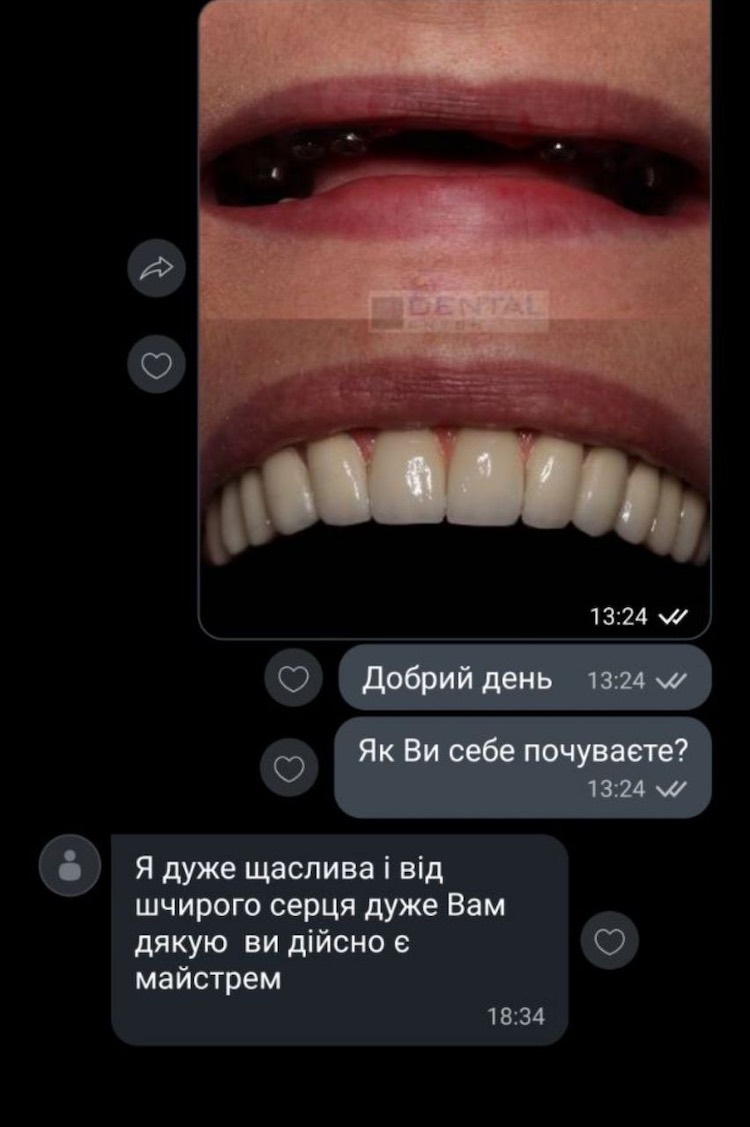

Фото отчет по имплантации верхней челюсти от 2024-01-04: было установлено 14 циркониевых коронок на 6 имплантах

«Я очень счастлива и от всего сердца очень Вас благодарю, вы действительно являетесь мастером»